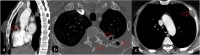

Hydatid cyst caused by the larval form of Echinococcus is a worldwide zoonosis. The lungs and liver are the most common sites involved. While the lung parenchyma is the most common site within the thorax, it may develop in any extrapulmonary region including the pleural cavity, fissures, mediastinum, heart, vascular structures, chest wall, and diaphragm. Imaging plays a pivotal role not only in the diagnosis of hydatid cyst, but also in the visualization of the extent of involvement and complications. The aim of this pictorial review was to comprehensively describe the imaging findings of thoracic hydatid cyst including pulmonary and very unusual extrapulmonary involvements. An outline is also given for the findings of complications and differential diagnosis of thoracic hydatid cyst.